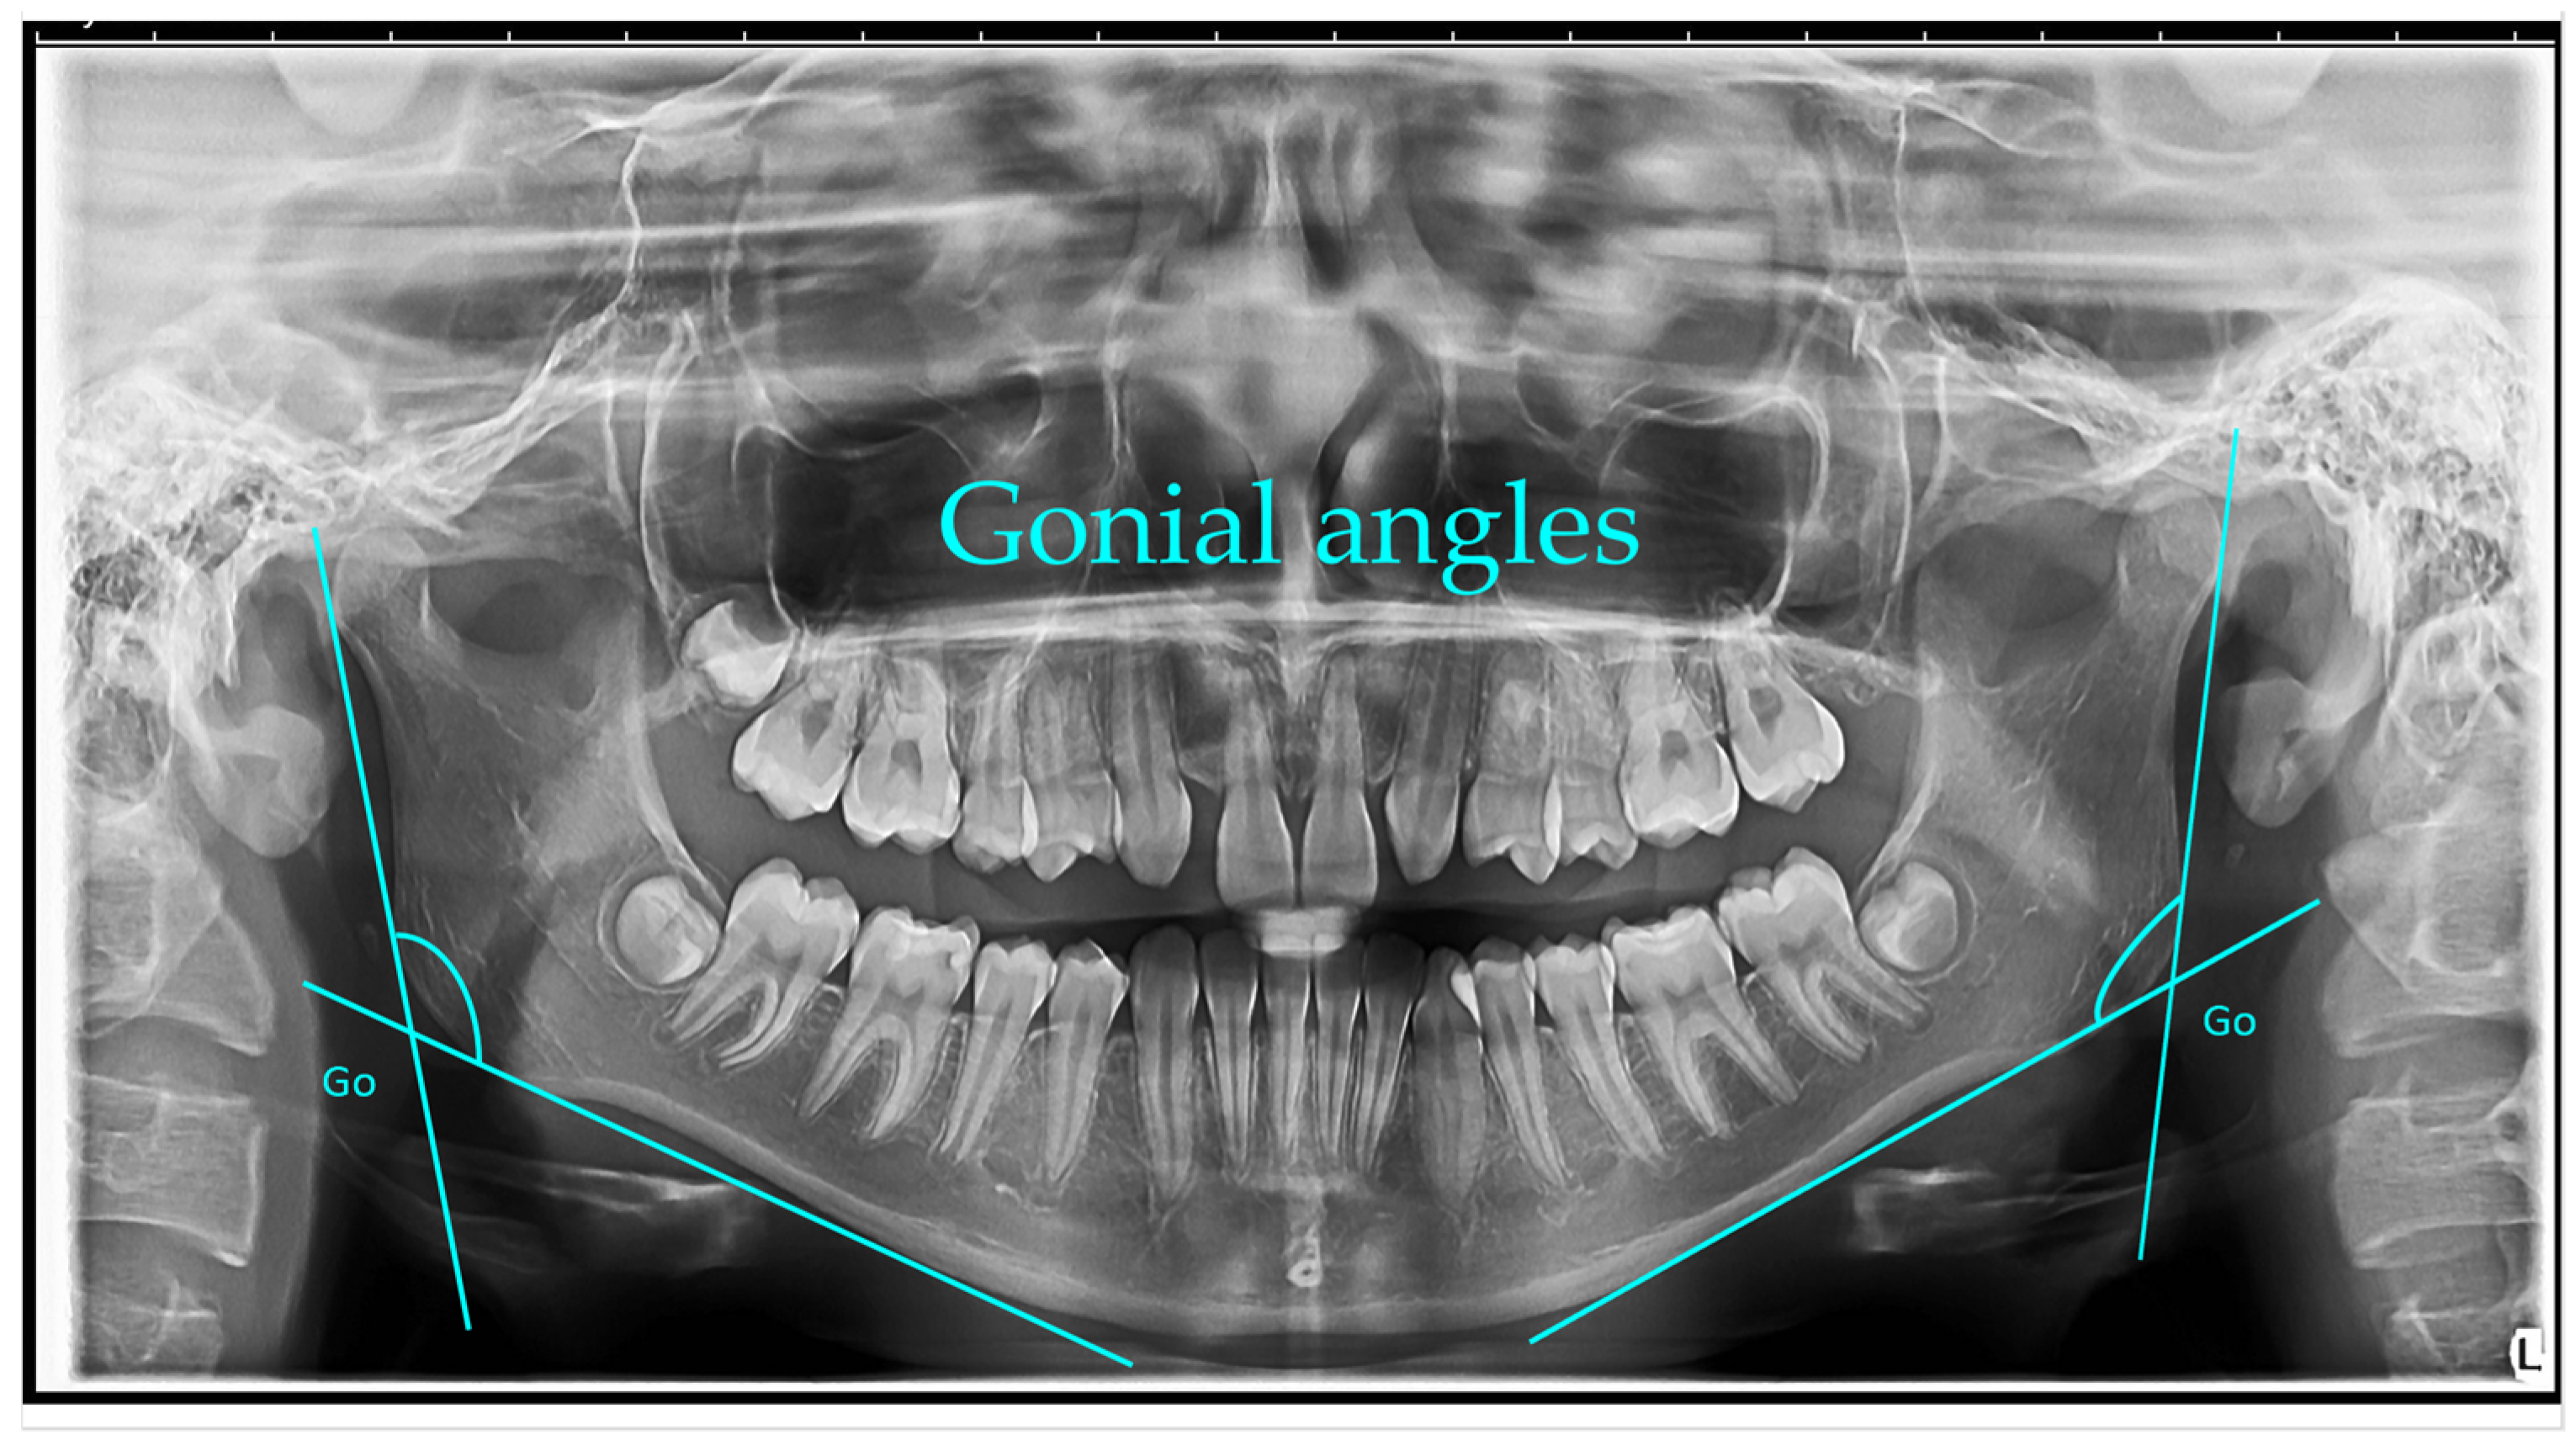

Gonial angle (left and right)—measured as the angle formed between a line along the lower border of the mandible passing through the condyle and a line along the posterior border of the ascending ramus. The mean gonial angle obtained from panoramic radiograph measurements was 122.74° (SD = 1.00°) overall, 122.84° (SD = 0.80°) for males, and 122.74° (SD = 1.00°) for females [1].

Gonial angle: The gonial angles were measured following the method described by Mattila et al. A line was digitally drawn on each panoramic radiograph tangential to the most inferior point at the gonial region and along the lower border of the mandibular body. A second line was traced tangential to the posterior borders of the ramus and the condyle. The intersection of these two lines defined the gonial angle, which was measured on the right or left side, depending on which provided the clearest image.

Figure 1, Figure 2, Figure 3, Figure 4, Figure 5 and Figure 6 illustrate the AI-assisted digital measurements exported from the WebCeph software, showing the identification of anatomical landmarks and linear or angular dimensions analyzed in this study.

Panoramic radiograph (orthopantomogram) illustrating the measurement of bilateral gonial angles. The gonion (Go) point was identified on both the right and left mandibular borders, and lines were drawn along the posterior border of the ramus and the lower border of the mandible to form the gonial angle. Both right and left gonial angles are indicated for comparative analysis (Figure 1).

Figure 1. Bilateral Gonial Angle Measurement on OPG. Go (gonion)—the most posterior, inferior, and lateral point on the mandibular angle. Lines were drawn along the posterior border of the ramus and the lower border of the mandible, intersecting at the gonial angle (°). Both right and left gonial angles are displayed for comparative analysis. Note: Images represent direct screenshots exported from the WebCeph® AI platform. Landmarks and measurement lines were automatically generated and manually verified by the authors.